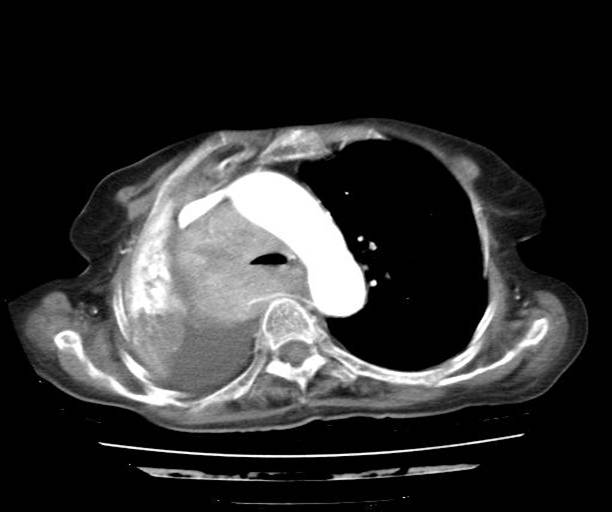

Chest Xray AP view

CT thorax